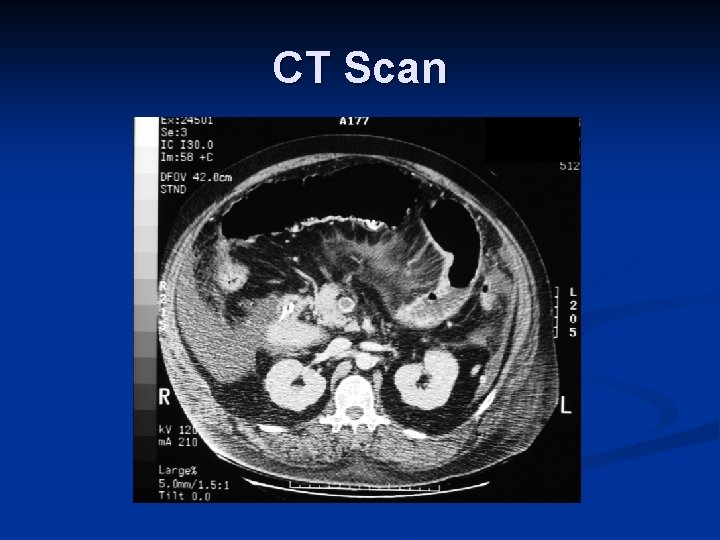

Imaging in Blunt Abdominal Trauma – CT Scan n Sensitivity: n Solid organ injury: 97% [II, III] n Identify Contrast extravasation n Guide Operative vs. Non-operative management n Enteric injury: 64 – 94% [III] n Diaphragmatic injury: 61% [III] n Pancreatic injury: 30% [III]

CT Scan

CT Scan

CT Scan

Learning Points Case #2 CT scan is helpful for decision making in a stable patient n Poor detection of hollow viscus, pancreatic and diaphragmatic injury n Be worried of free fluid in abdomen n Repeat CT Scan and close clinical observation n